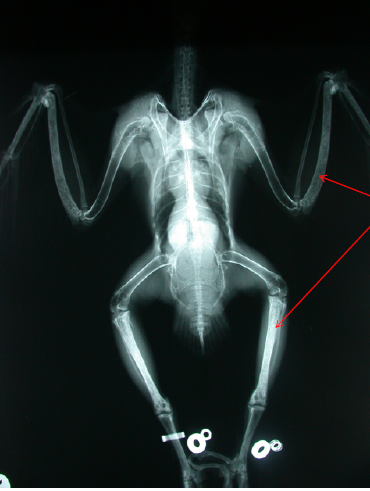

What happened?

What material is involved?

Would you treat surgically?

Shotgun pellets (from some dipshit)

Steel (smooth/round edges)

Would NOT treat surgically–too many/too deep; body just walls off foreign material